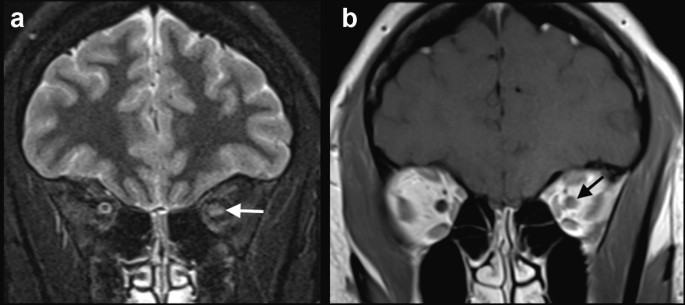

Case 6: A 33-year-old previously healthy man presented with fever for one week, associated with a positive nasal swab for SARS-CoV-2. After 2 weeks, he started with bilateral facial nerve palsy. Brain MRI, performed 3 days after the neurological symptoms onset, demonstrated gadolinium enhancement in the canalicular and labyrinthine portions of the facial nerves (Fig. 6). The patient was also treated with oral prednisone, 60 mg/day, for 7 days, with complete recovery.

Fig. 6

figure 6

COVID-19 associated with bilateral facial nerve palsy. Brain MRI showed bilateral gadolinium enhancement in the canalicular and labyrinthine portions of the facial nerves, on T1-3D MPRAGE (arrow in a) and coronal fat saturation T1-weighted spin-echo imaging (arrow in b)